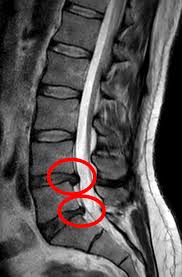

Coloana vertebrală este formată din vertebre între care există discuri intervertebrale. Aceste discuri funcționează ca niște amortizoare.

Hernia de disc apare atunci când o parte din nucleul pulpos iese prin inelul fibros și poate irita sau comprima o rădăcină nervoasă.

Studiile arată că foarte multe persoane au hernii de disc fără să aibă simptome. Imagistica (RMN sau CT) descoperă frecvent hernii chiar și la oameni fără durere.